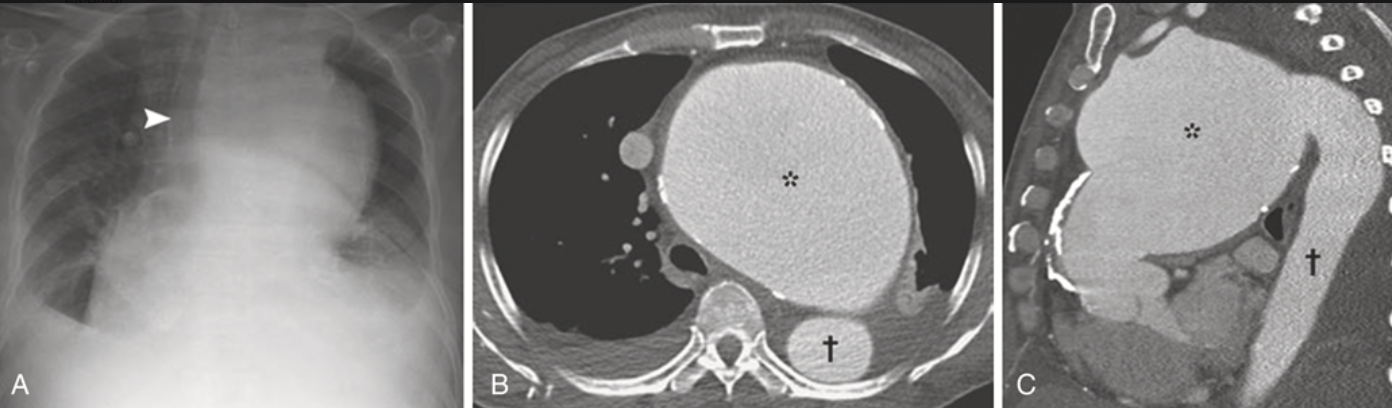

① 近位大動脈の拡張、上行大動脈の前外側壁の線状石灰化(古典的なXp所見)

動脈瘤は50%は上行大動脈弓に生じ、巨大化しても症状に乏しいため”aneurysm of sings”と呼ばれる。ついで30-40%は横行弓に生じ、縦隔内の構造物に隣接するため”aneurysm of symptoms”と呼ばれる。